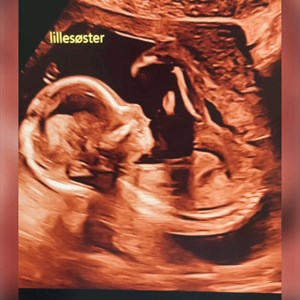

Ét af mandagens besøg 🫶🩷 Sød lille pige. 15 uger og kampvægt på ca 120 gram. Hun er så ...